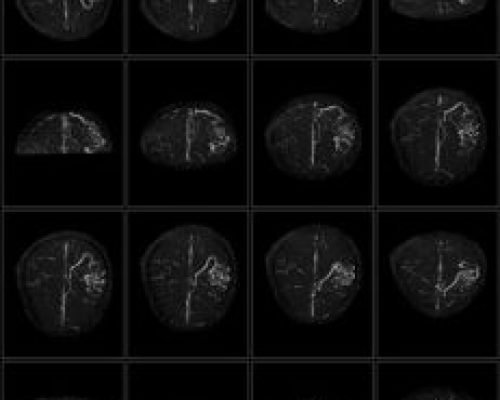

The PICA MRI system is our flagship product with its unique open architecture, advanced hardware platform and leading-edge clinical applications make it ideally suited for patient comfort, fast acquisition times and excellent image quality. The PICA has passed all ACR Accreditation requirements of 4 MRI modules: Head, Spine, Body and MSK. This accreditation also means that patient scans from PICA is approved for financial reimbursement by the US Government MEDICARE program as well as private insurance companies in the US.

- Strong Gradients for High-Resolution Image Acquisition

High-performance gradient hardware ensures clear, sharp imaging even at 0.35T.